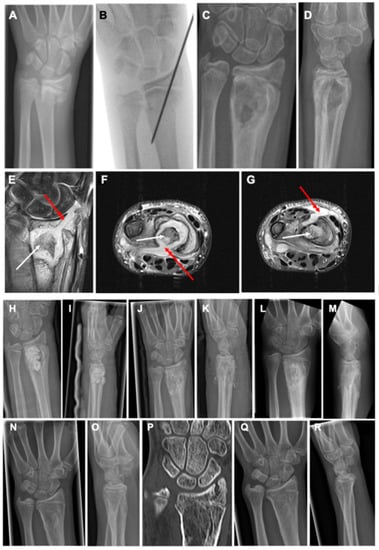

Figure 1. A 13-year-old male patient sustained a dislocated fracture of the distal radius and an undislocated distal ulna fracture after a bicycle accident (A). Closed reduction and percutaneous K-wire fixation was performed with epicutaneous placement of the K-wire (B). Four weeks after surgery, the boy presented with acute redness and swelling at the distal forearm with high suspicion of a fracture-related infection. The K-wire was completely loosened and removed before X-ray control (C,D). X-rays showed a healed fracture with severe osteolysis in the metaphyseal region with accompanying periosteal reaction. MRI confirmed severe osteolysis in the metaphyseal region with more details, such as abscess and sequestrum formation (white arrows) and affection of the growth plate and epiphysis through the channel, where the K-wire had initially been placed on coronal views ((E), red arrow). Although the initial K-wire placement had violated the radiocarpal joint, no signs of septic arthritis of the wrist joint were detected. Axial MRI images showed cortical lysis at the metaphyseal area with abscess penetration into palmar ((F), red arrow) and dorsal ((G), red arrow) soft tissue structures. Treatment consisted of a two-stage procedure with debridement and sequestrectomy, partial synovectomy, and insertion of an antibiotic-loaded PMMA spacer at stage 1 (H,I). After 4 weeks, the spacer was removed and the defect was filled with autogenous bone graft from the ipsilateral iliac crest (J,K). After six weeks, the bone grafting procedure showed good new bone formation in the former infected defect area without recurrence of infection but with first signs of premature closure of the ulnar aspect of the epiphyseal growth plate (L,M). After a total of six months after bone grafting, the metaphyseal bone showed complete healing with remodeling of the cortical area and disappearance of the initial periosteal reaction with progressive closure of growth plate with correct alignment of the distal radioulnar joint (N,O). CT scan on the same day confirmed the successful bone regeneration in the metaphyseal zone with remodeling of the cortical area complete and premature closure of approximately 80% of the epiphyseal plate with still correct appearance of the distal radioulnar joint (P). At the 18 months follow-up, premature arrest of the epiphyseal plate resulted in an ulna plus variant of the wrist joint (Q,R).

Treatment consisted of a two-stage procedure with debridement and sequestrectomy, and partial synovectomy, and the insertion of an antibiotic-loaded polymethyl methacrylate (PMMA) spacer (mixture: 40 g Copal®, Heraeus, Wehrheim, Germany + 2 g vancomycin powder) at stage 1 via a modified Henry approach was performed. Approximately, 7.5 cc of the antibiotic-loaded PMMA was used. In addition, a 2 cm lateral approach to the processus styloideus radius was needed for full soft tissue and bone debridement. Deep tissue samples taken intraoperatively from the deep soft tissue layer and the bone revealed culture growth of Staphylococcus aureus. After 4 weeks, the spacer was removed and the defect was filled with autogenous bone graft from the ipsilateral iliac crest. The patient received cefazolin (100 mg/kgKG) three times daily i.v. for a duration of seven days according to the resistogram of the pathogen. Sport activities were restricted for three months.

The patient remained infection free, and after six weeks, the bone grafting procedure showed good new bone formation in the former infected defect area without recurrence of infection but with the first signs of premature closure of the ulnar aspect of the epiphyseal growth plate.

After a total of six months after bone grafting, X-ray control showed the metaphyseal bone with remodeling of the cortical area and disappearance of the initial periosteal reaction. However, progressive closure of the growth plate had also to be noted. At the 18 months follow-up, premature growth arrest of the epiphyseal plate resulted in an ulna plus variant of the wrist joint. The patient had a range of motion of extension/flexion of 45-0-70° with full pro- and supination.